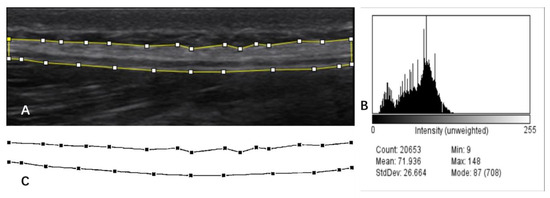

TLF is a fibrous connective tissue composed of collagen (3) that appears as a highly echogenic layer in ultrasound images [30], and it has a clear border in contrast to subcutaneous tissue (fat) as well as muscle (Figure 2). As shown in Figure 3A, one researcher completed manual labeling of all TLF cross-sectional areas (CSA) using ImageJ software (United States National Institutes of Health; Bethesda, MD, USA). Offline assessment of the echogenicity and tissue homogeneity within TLF CSA (Figure 3B) were obtained, and the mean value of echo intensity of TLF CSA was taken for data analysis. This measurement of echo intensity has been widely used in skeletal muscle research [31].

Fascia Thickness Measures

Previous studies have mainly used the fascial thickness of a single location or the mean value of several areas for data analysis [8,29]. This does not give an actual average of TLF thickness. To obtain the average thickness of the TLF more accurately, we developed a Python-based method for collecting fascia thickness. First, get a hyperbolic diagram (Figure 3C) of the TLF of CSA obtained after texture extraction by AI imaging software (version 1. Yongzhou, China). Next, the image was converted to grayscale and binarized using Python programming (version 3.6.4). Programming with programming languages, each pixel on the grayscale image was sampled, and the distance between the top and bottom of the hyperbola was calculated and divided by the number of horizontal pixels (sampling points). The calculation result is based on the reference scale of the original image.